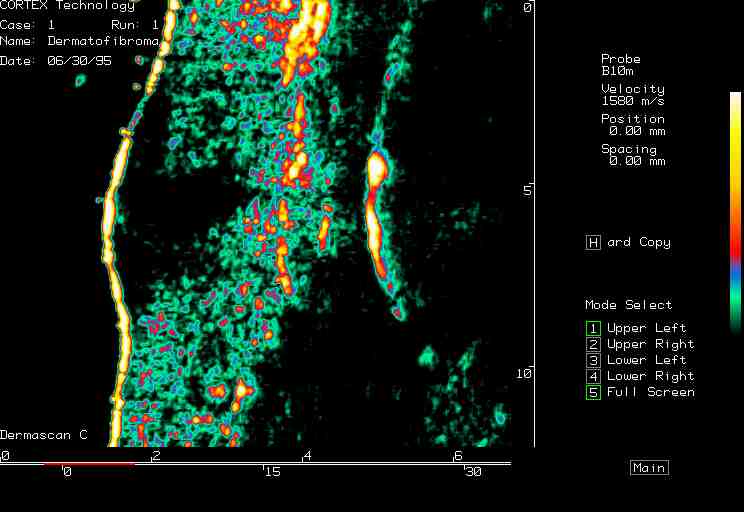

| Dermatofibroma, nevus |  Dermatofibroma |